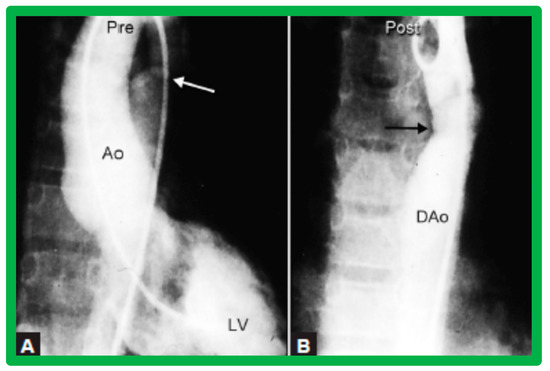

4.2. Aortic Stenosis

6.2.1. Residual Gradients